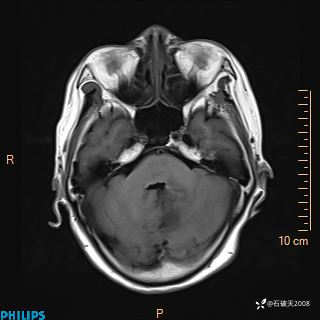

书上说这个肿瘤发生在幕下仅4.09%,你会想到它吗?(病理已公布)

增强轴位